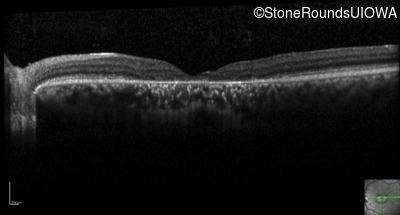

Optical Coherence Tomography - Left - 20/100

Exemplar / OCT Stack

OCT Stack